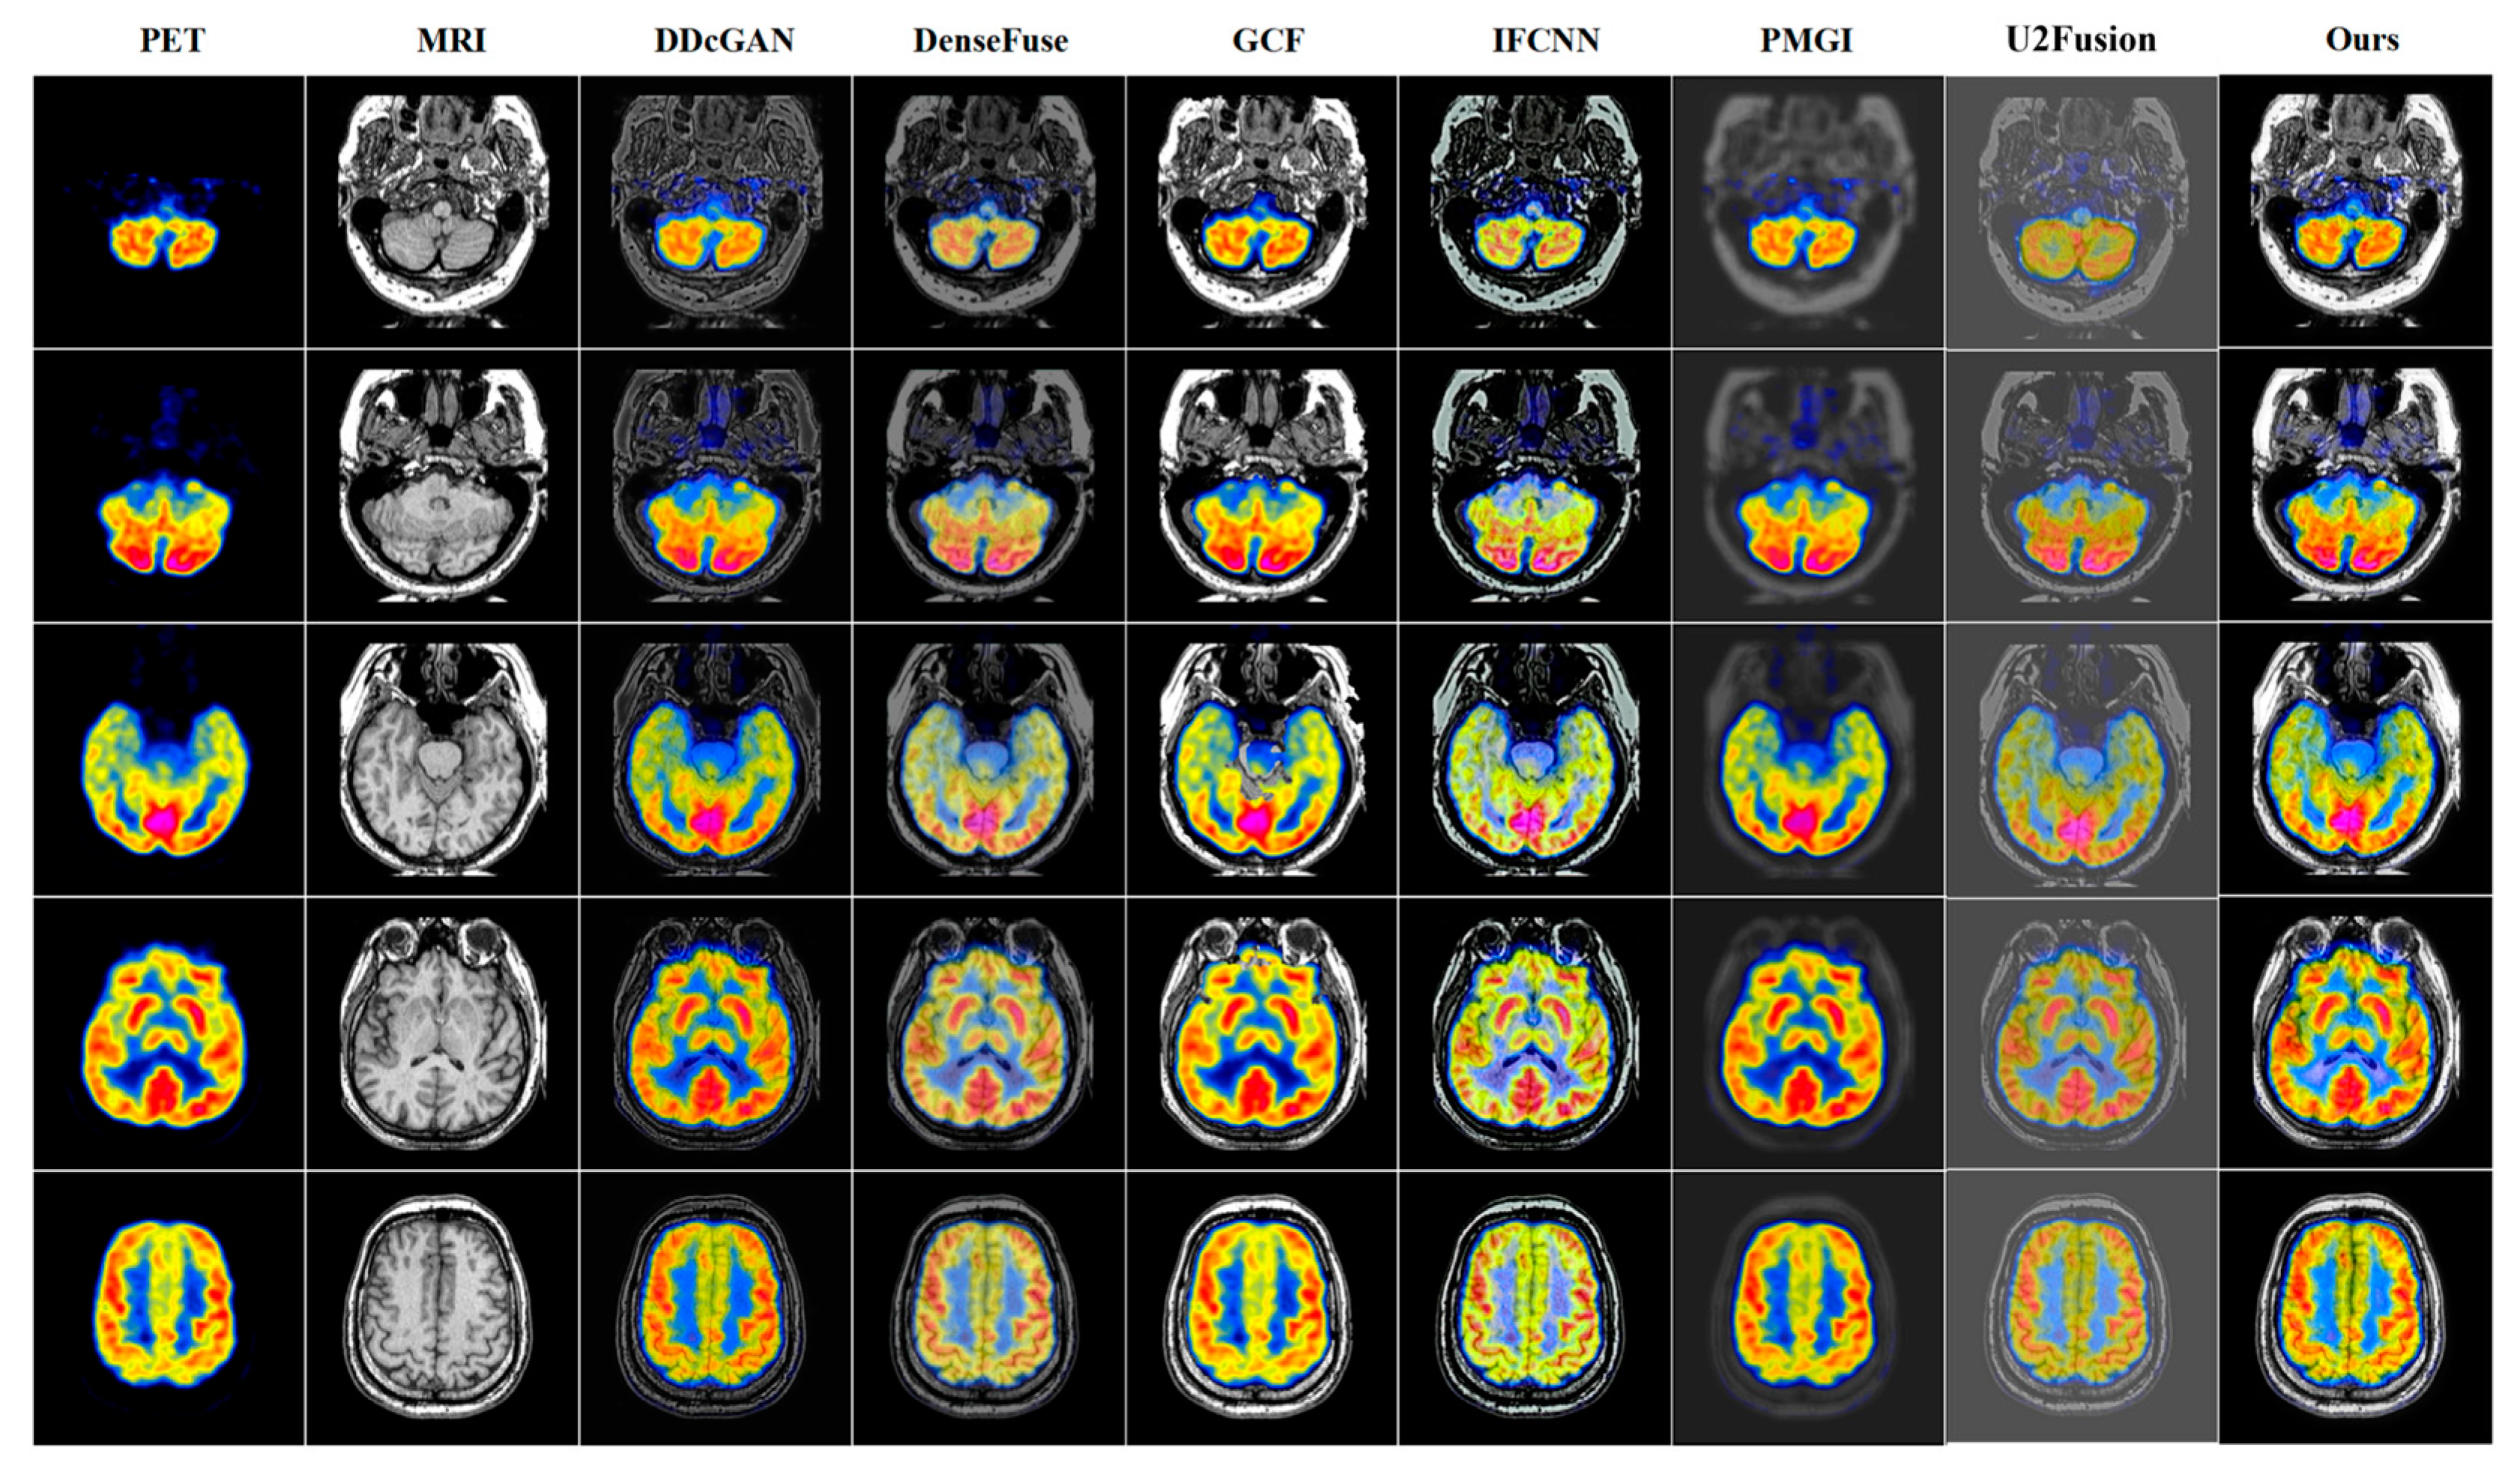

4.3. Quantitative and Qualitative Comparison Results

PET-MRI | DDcGAN | DenseFuse | GCF | IFCNN | PMGI | U2Fusion | Ours |

---|---|---|---|---|---|---|---|

AG↑ | 6.0128 | 4.9272 | 7.0089 | 6.9044 | 2.7804 | 3.8598 | 8.3813 |

EI↑ | 60.3775 | 51.1228 | 75.6065 | 73.8009 | 29.6103 | 40.6413 | 84.7561 |

Qabf↑ | 0.3655 | 0.2863 | 0.5848 | 0.5026 | 0.1736 | 0.1705 | 0.6456 |

Qcv↓ | 1577.441 | 947.514 | 718.393 | 412.393 | 3667.634 | 1861.1615 | 220.779 |